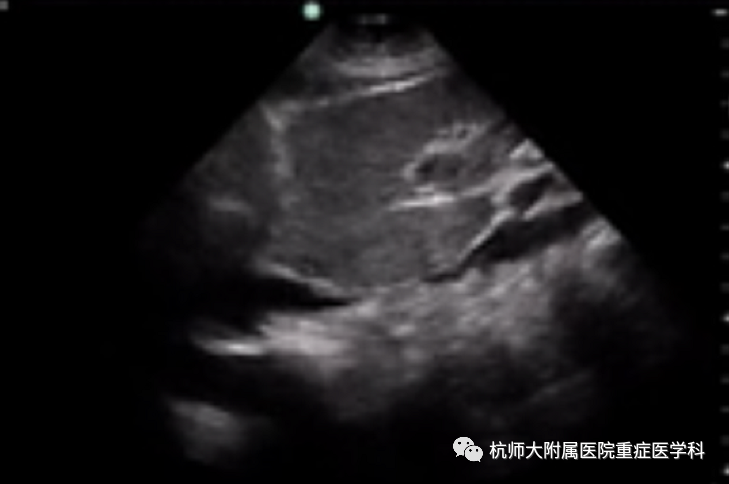

g.剑突下四腔心切面:位置选择:剑突下,超声探头声束朝向与房间隔平行,超声探头标记点指向左侧;操作中:(1)滑:超声探头从腹部向剑突下水平滑动;超声探头标记点指向受检者左侧;(2)倾:超声探头从水平方向缓慢向上倾斜,显露心脏;

什么是超声容积探头重症心脏超声图像的获取_https://www.jmylbn.com_新闻资讯_第25张什么是超声容积探头重症心脏超声图像的获取_https://www.jmylbn.com_新闻资讯_第26张

主要评估内容:(1)心包积液检查;(2)观察四个腔室及二尖瓣、三尖瓣的结构与运动;(3)评估右心室室壁厚度、房间隔缺损的最佳切面。